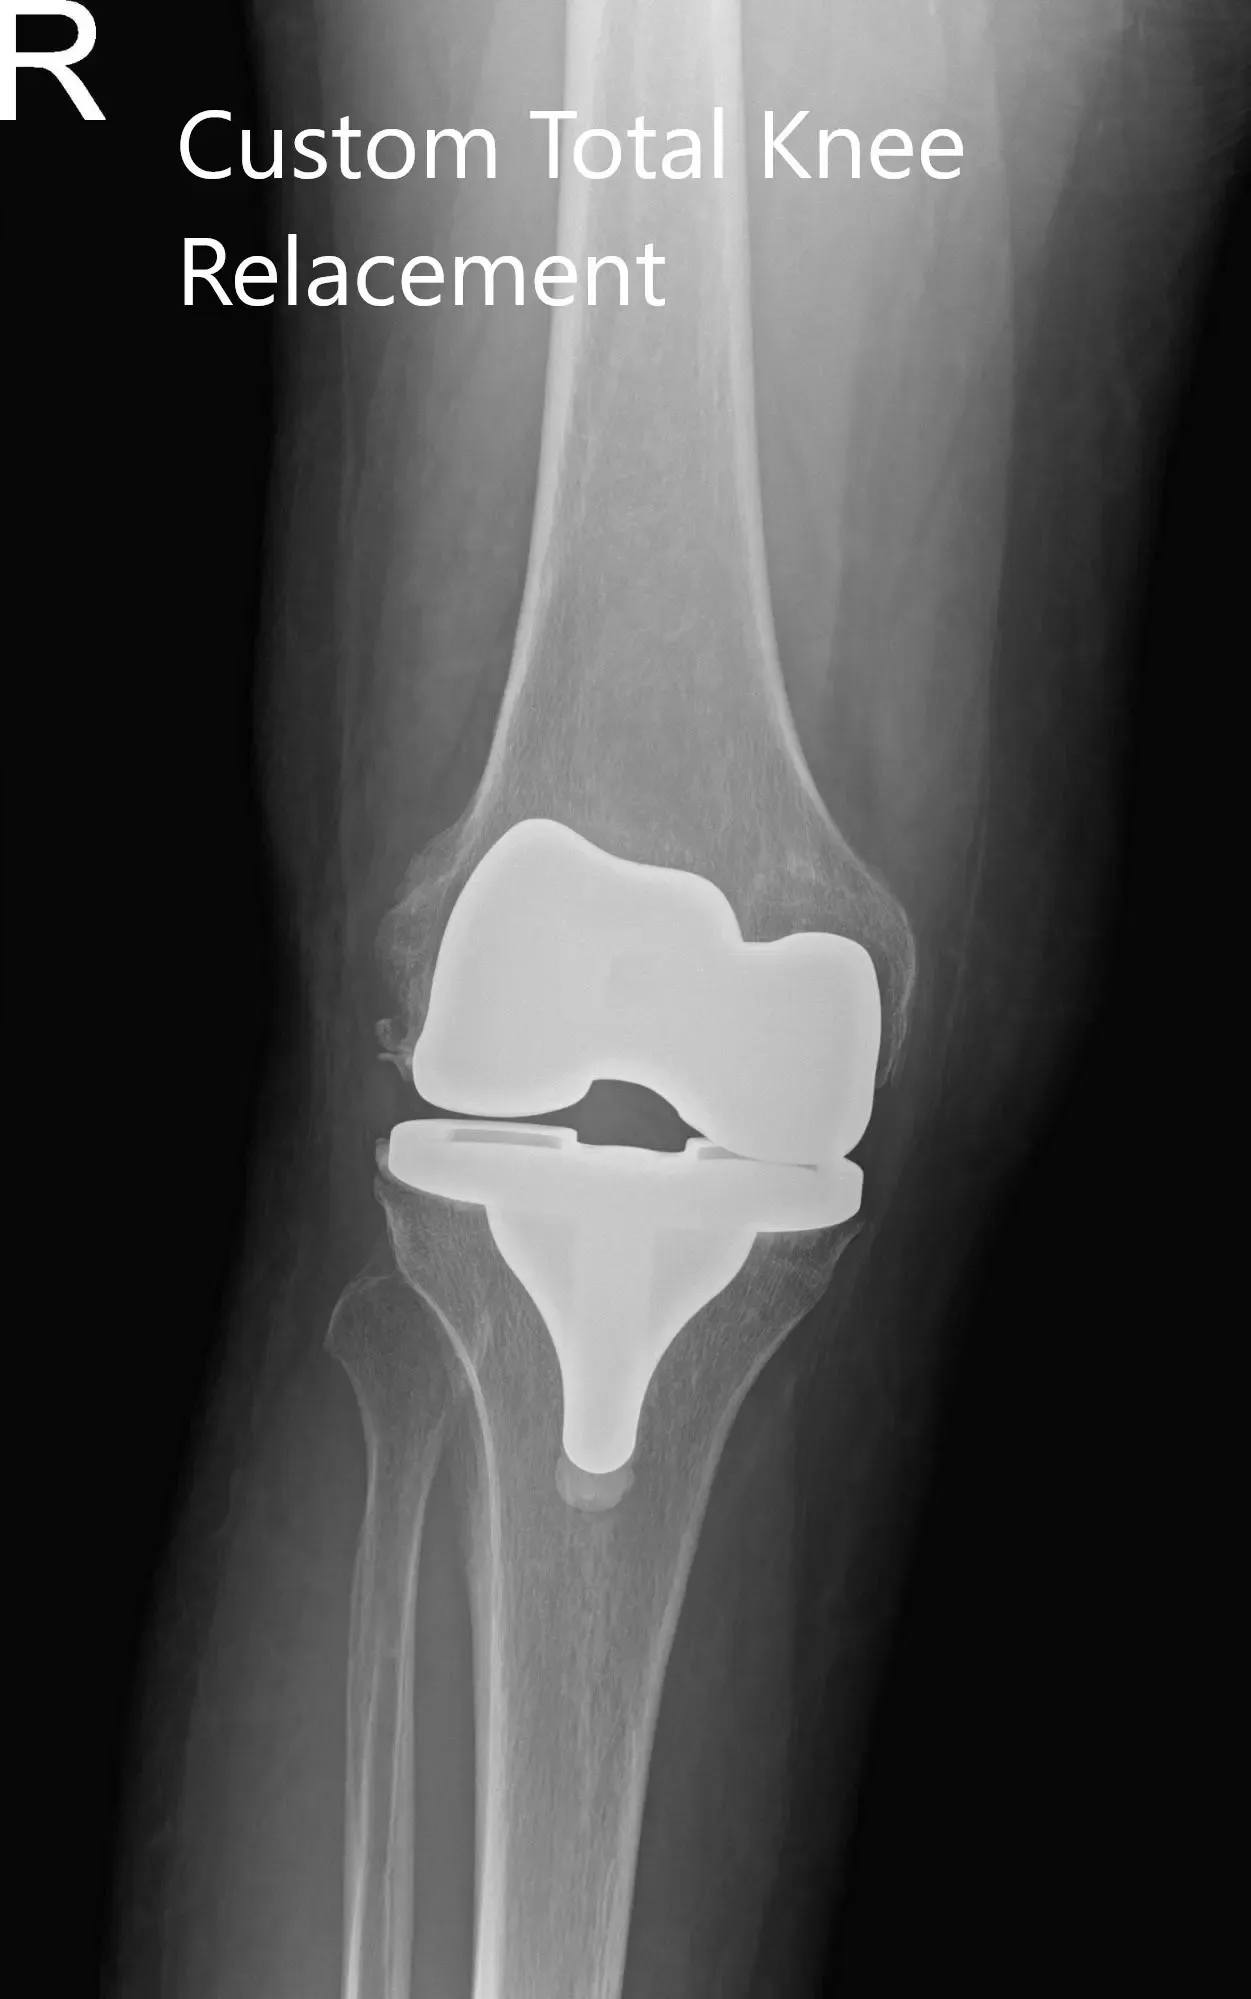

El implante utilizado: Implante femoral personalizado con una bandeja tibial personalizada con inserto de polietileno de 6 mm y rótula de 32 mm x 8,5 mm.

Radiografía postoperatoria del paciente que mostró visión AP y lateral de la rodilla derecha